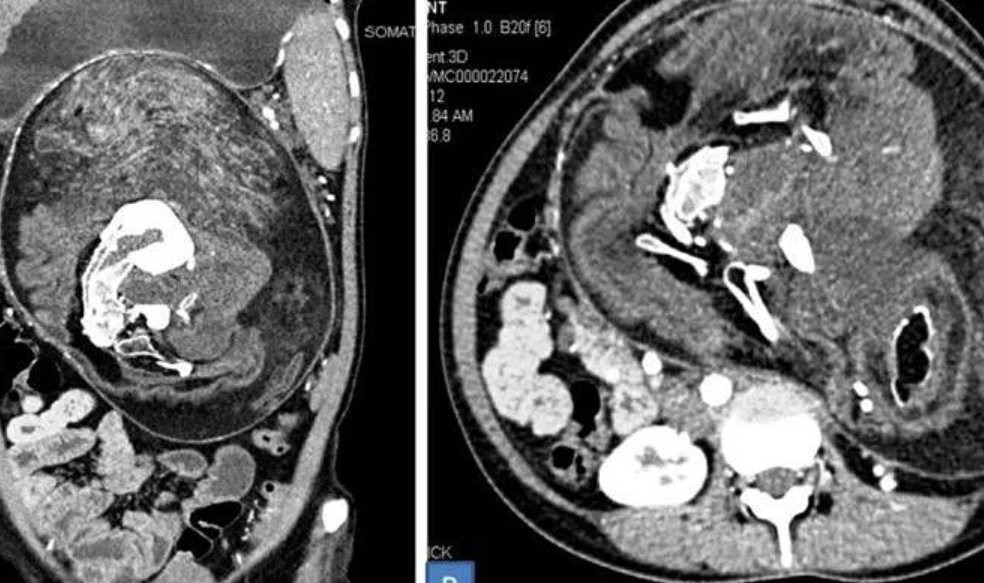

Ảnh chụp CT khối thai song sinh trong cơ thể cô gái. (Ảnh: BMJ Case Reports)

Hai thai song sinh đã bị biến dạng song vẫn đang phát triển trong bụng cô gái 17 tuổi. Ban đầu kiểm tra, các bác sĩ không nhìn rõ bào thai.

Kiểm tra kỹ hơn, họ khẳng định là thai nhi dù không hoàn chỉnh, với xương đốt sống, xương sườn và xương đùi. Ngoài ra, bào thai còn có tóc và răng, cùng những cấu trúc mô không định hình mà nếu phát triển bình thường sẽ thành những bộ phận cơ thể trẻ sơ sinh.

Bác sĩ xác định đây là hiện tượng thai trong thai, xảy ra một trong số 500.000 ca sinh sản trên thế giới. Tình trạng thai trong thai thường gặp ở trẻ trai, được phát hiện sớm và hiếm khi vượt quá thời thơ ấu.